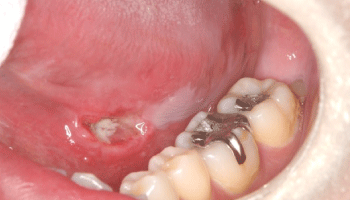

ニコチン性口内炎とは - 医療総合QLife。

ニコチン性口内炎」になるとどのような症状が出るかご存じですか? 医師監修メディカルドック。

ニコチン性口内炎大東市・野崎駅前歯科クリニック・治療大解説。